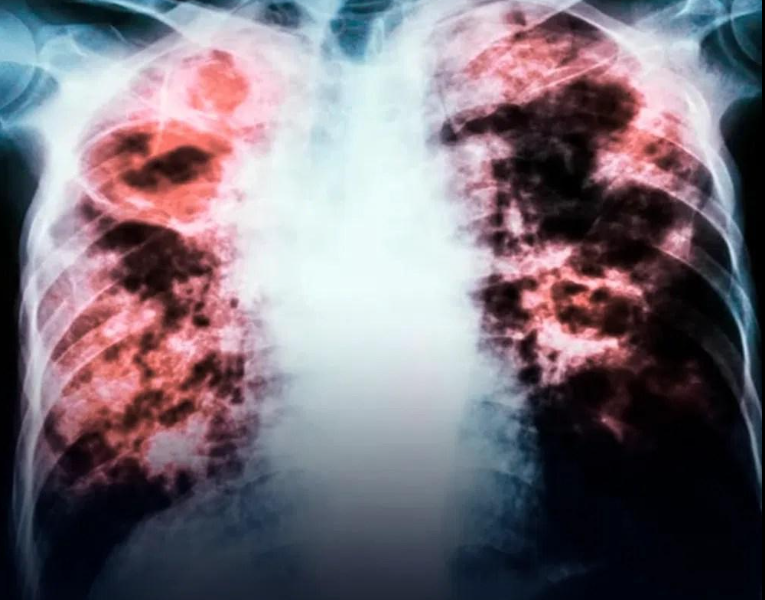

Lungenkrebs wurde traditionell mit Rauchen in Verbindung gebracht; in den letzten Jahrzehnten ist jedoch ein starker Anstieg der Fälle bei Nichtrauchern zu verzeichnen. Dieses Phänomen hat Forscher veranlasst, andere Risikofaktoren wie Umweltverschmutzung, Chemikalienbelastung und genetische Veranlagung zu untersuchen, die die Krankheitsentwicklung beeinflussen könnten.

Lungenkrebs ist definiert als die unkontrollierte Vermehrung von Zellen im Lungengewebe, die die Atemfunktion beeinträchtigt. Obwohl Tabakkonsum weiterhin der Hauptrisikofaktor ist, treten 10 bis 20 % der bestätigten Fälle bei Nichtrauchern auf. Laut der erwähnten Studie ist das Adenokarzinom der häufigste Subtyp, insbesondere bei Frauen (59,7 % der weiblichen Fälle), während es bei Männern 45,6 % der Fälle ausmacht.